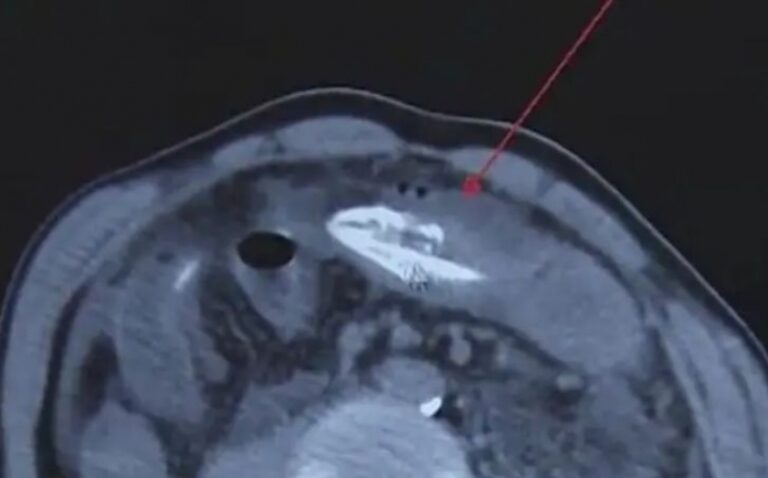

Muškarac je zamalo umro nakon što je u rektum umetnuo jegulju od 20 centimetara u čudnom pokušaju da se izbori sa “tvrdom stolicom”.

U julu, nakon što je pokušao primijeniti “stari narodni lijek” sa jeguljom, za koji se tvrdi da će pomoći pri pražnjenju crijeva, muškarac iz Xinghua, istočna Kina, umalo je izgubio život. Jegulja se, naime, premjestila iz rektuma u debelo crijevo i prožvakala ga, pristupajući abdomenu.

Hirurzi su uklonili još uvijek živu jegulju, ali su obavijestili čovjeka da je mogao umrijeti od hemolize, koja se događa kada se crvena krvna zrnca unište nakon što bakterije iz debelog crijeva dođu do želuca, piše Unilad.